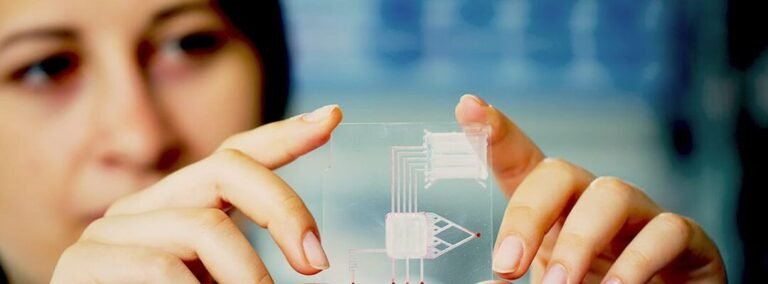

2. Nanoestructuras y biomimetismo

Las nanoestructuras diseñadas para imitar la arquitectura natural del hueso juegan un papel crucial en la ingeniería de tejidos. Por ejemplo, los andamios nanofibrosos replican la matriz extracelular, proporcionando un microambiente adecuado para la migración y proliferación de osteoblastos, esenciales en el papel de la nanotecnología en la ingeniería de tejidos óseos.

A pesar de los avances, la implementación clínica de la nanotecnología en la ingeniería de tejidos óseos enfrenta desafíos, como la escalabilidad y la evaluación de toxicidad a largo plazo. Sin embargo, estudios preclínicos muestran resultados prometedores en la reparación de defectos óseos críticos.